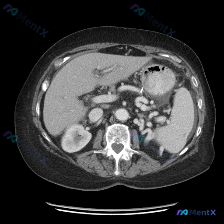

看到一个病例资料挺有意思,整理了一下思路和大家讨论。 用户最初的问题是“图中观察到的特定异常是什么?脾脏病变”,等于先给了一个“存在脾脏病变”的前提。但拿到这张上腹部CT横断面图像(倾向于增强扫描的动脉期或门脉期),仔细看下来,情况其实不太一样。 --- 先看影像层面的客观发现: - 扫描质量与层面...

最近看到一个有意思的影像病例,预设是要讨论「脾脏病变」,但看完影像报告和分析后,发现核心其实是「澄清矛盾」,整理一下思路和大家分享。 --- 先看完整的影像观察结果 这是一份腹部CT横断面的分析: - 实质脏器:肝、胰、脾、肾都大致正常——肝脏密度均匀,胰周脂肪间隙清晰,脾脏形态/大小正常、密度均匀...

今天看到一个有意思的影像读片案例:提问直接预设了“脾脏病变”,但仔细看完提供的资料,发现情况好像不太一样。整理了一下思路,和大家分享。 先看影像资料(客观描述) 这是一张上腹部CT横断面软组织窗影像,报告里的客观表现: - 肝脏:形态尚可,密度基本均匀,未见明确异常高低密度占位,边缘清晰,血管走行正...

今天看到一份很有意思的影像资料,提问直接指向“脾脏特异性异常”,但仔细读完图像和分析,发现里面藏着一个很典型的临床思维陷阱,整理一下思路和大家分享。 先看这张CT的客观发现 这是一张腹部CT横断面软组织窗图像: 1. 脾脏:形态可见,密度均匀,没有看到明确的增大,也没有局灶性的高低密度病变; 2....

整理了一份有点「反转」的影像读片资料,感觉挺考验临床思维的,分享出来一起理理思路。 --- 一、影像基本信息 这是一张腹部CT横断面软组织窗图像,预设的观察焦点是「脾脏病变」。 二、结构化读片所见(客观描述) 按照读片常规扫了一遍全腹: 1. 肝脏、胆囊、胰腺:形态、大小、密度都正常,轮廓光滑,胰周...

今天看到一个很有意思的影像分析场景,整理一下思路和大家分享。 --- 病例背景 用户提供了一张腹部CT横断面(软组织窗),并直接询问:“图片中可见的特殊异常是什么?脾脏病变”。 影像核心表现 我先按标准流程梳理了这张CT的关键信息: 1. 脾脏:大小、形态正常,脾实质密度均匀,明确未见占位、梗死或异...